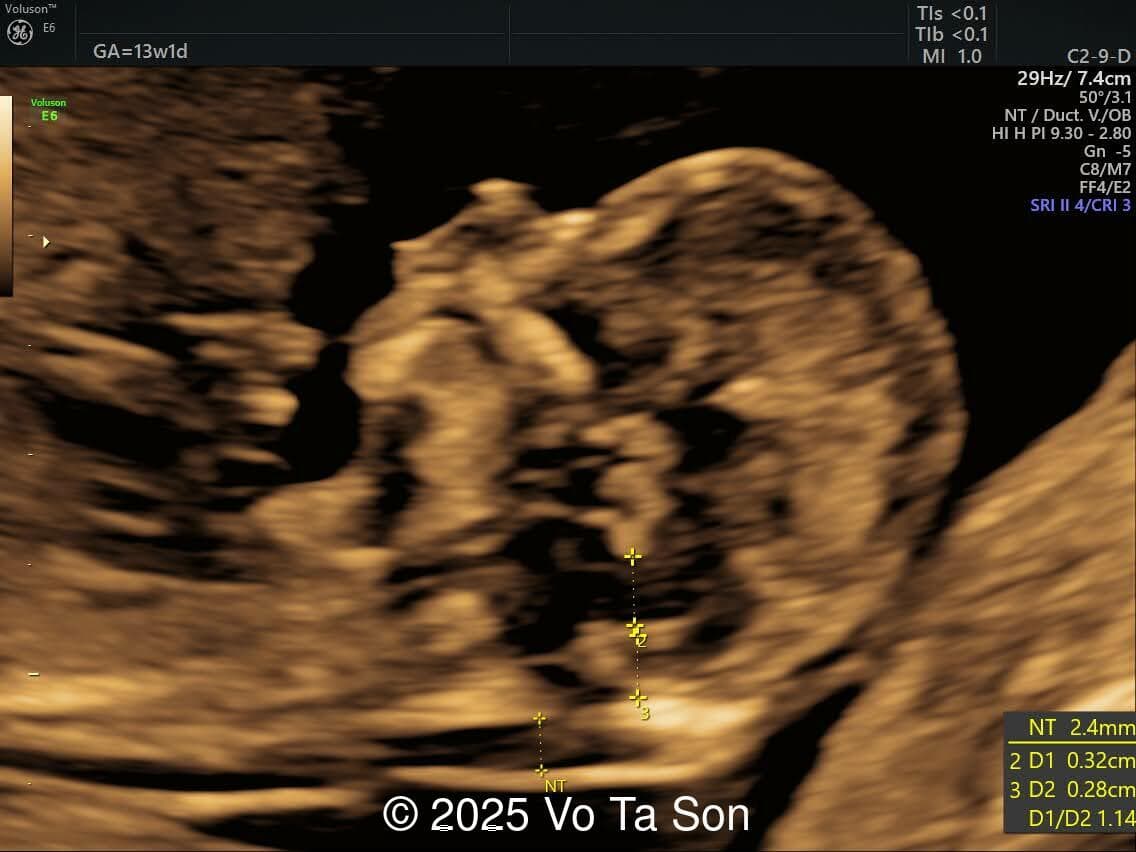

A 13-week pregnant woman underwent routine prenatal screening. The non-invasive prenatal test (NIPT) showed low risk for common aneuploidies (trisomy 21, 18, and 13). However, first-trimester anomaly scan revealed the following significant fetal abnormalities:

- Thin nasal bone